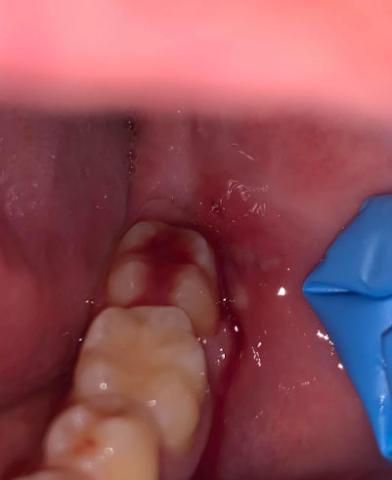

Bleeding Gums in Teenager Molar Area - Zoomed Dental Case Analysis

Focused Area: Posterior molar region and surrounding gum tissue (teenage patient)

Observed Findings

Localized active gum bleeding adjacent to the molar

Red and inflamed gingival tissue, indicating irritation

Presence of plaque accumulation along the gum margin

Area is anatomically difficult to clean, increasing bacterial retention

Tooth crown appears intact with no obvious fracture visible at this magnification

Probable Diagnosis

Plaque-induced gingivitis in the molar region

Localized gingival inflammation, possibly aggravated by poor oral hygiene

Early periodontal risk if untreated